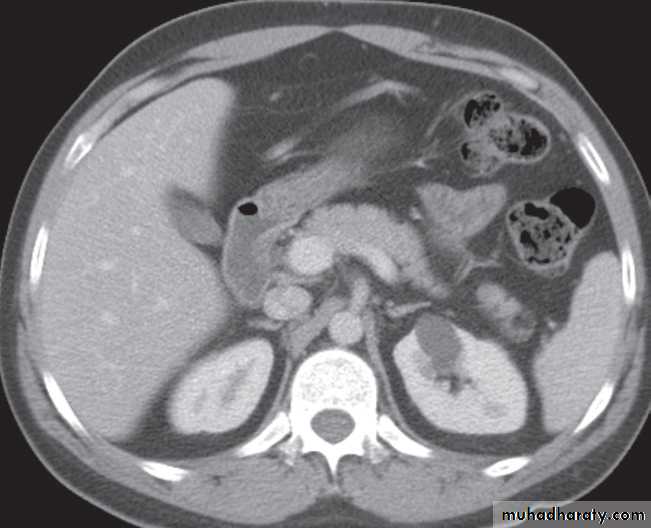

-Renal cell carcinomas are approximately spherical and often lobulated .With density similar to renal parenchyma or slightly less with often seen some areas of necrosis & calcification .

Staging of renal cell carcinoma is usually undertaken with CT, the current method of choice .

Wilms’ tumour is the likely diagnosis in a child with a renal mass. These lesions are frequently large and may contain stippled calcification